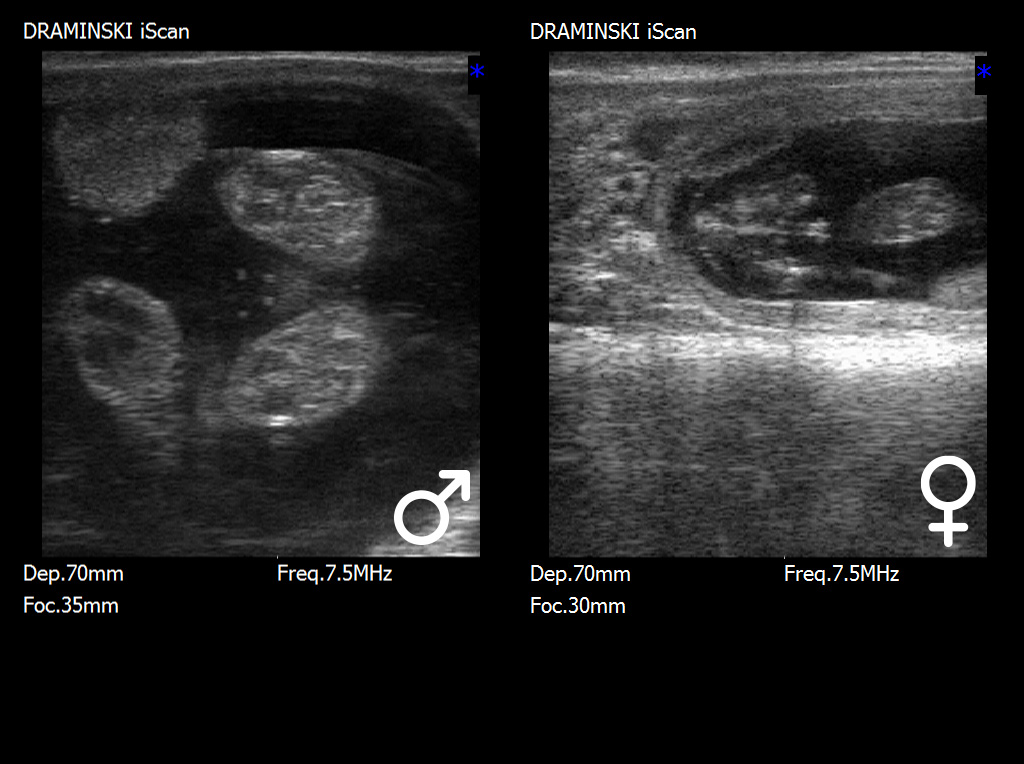

W tym etapie rozwoju kluczową strukturą diagnostyczną jest guzek płciowy (tuberculum genitale), który ulega charakterystycznemu przemieszczeniu w zależności od płci. U płodów męskich guzek płciowy przemieszcza się w kierunku pępka i przyszłego prącia, natomiast u płodów żeńskich lokalizuje się bliżej ogona, w rejonie przyszłego sromu. Prawidłowa interpretacja położenia tej struktury wymaga nie tylko dobrej jakości obrazu ultrasonograficznego, lecz także odpowiedniego doświadczenia badającego, ponieważ niewielkie różnice w ułożeniu płodu mogą wpływać na ocenę.

W późniejszym okresie ciąży, po około 70.–80. dniu, możliwa jest identyfikacja bardziej wykształconych narządów płciowych, takich jak moszna u płodów męskich lub struktury sromu u płodów żeńskich. Choć w tym czasie cechy płciowe są bardziej widoczne, to jednocześnie badanie staje się trudniejsze ze względu na zwiększające się rozmiary płodu, jego głębsze położenie w jamie macicy oraz ograniczoną możliwość manewrowania głowicą ultrasonograficzną.